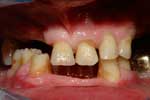

Caso 16

Riabilitazione superiore su impianti con protesi parzialmente rimovibili ed inferiore su impianti fissa

Caso iniziale